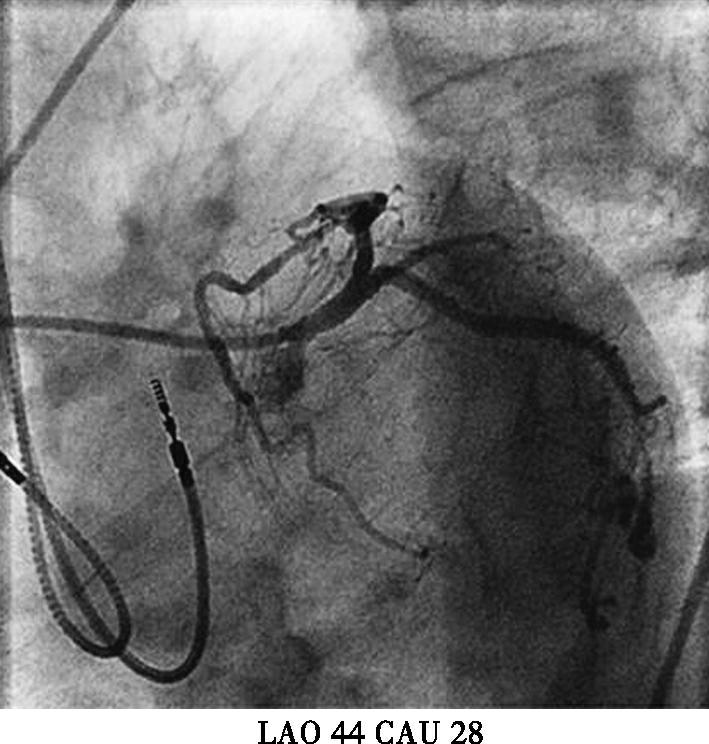

本例患者虽然有高血压、糖尿病等冠心病危险因素。起搏器电极植入后立刻发生的胸痛考虑与心绞痛关系不大,且患者未出现心电导联ST-T变化,胸痛原因主要考虑:起搏电极导致冠脉损伤?起搏电极刺破右室?遂台上决定立即行冠脉造影(图3);多个投照体位均可见起搏电极螺旋尖端触及前降支,因此决定行前降支血管内超声(IVUS)检查,结果于电极接触部位,血管8点钟方向可见强回声,距离血管外膜小于1mm;综合判断起搏电极损伤血管外膜导致胸痛的可能性大;随后进行电极重新植入,并再次造影排除起搏电极穿透冠脉可能,电极具体位置及冠脉造影见图4,心室起搏参数(阈值0.8V,阻抗670Ω,R波10.0mv)。患者症状完全消失,于导管室留观30分钟,复查心脏超声,心包内未见积液,排除起搏电极刺破右室可能,转回病房。

图3初次植入心室电极后冠脉造影